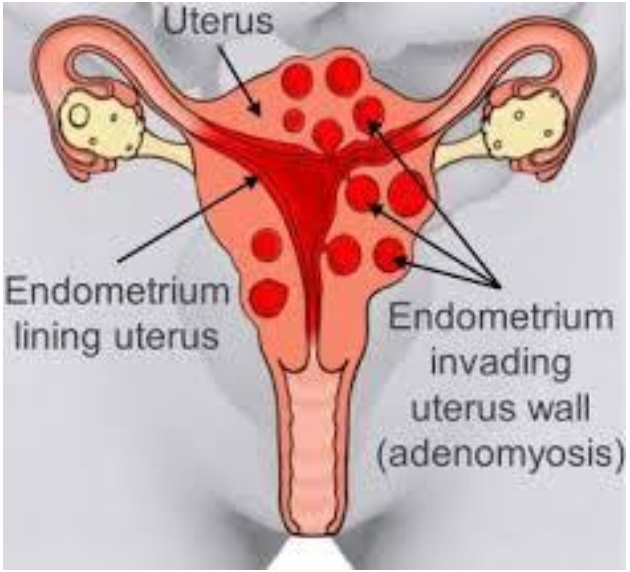

Benign disease

Diffuse or focal

Global infiltration of endometrium

Sonographically presents as bulky enlarged uterus without focal mass

Adenomyosis is ectopic occurrence of endometrial tissue within myometrium; more common in

posterior aspect

The tissue penetration usually reaches a depth of at least 2.5 mm from the basal layer of the

endometrium.

Adenomyosis may arise from multiple pregnancies and deliveries with subsequent uterine shrinking.

Elevated estrogen levels may also promote the growth of myometrial islands of endometrial tissue.

Adenomyosis is often classified into diffuse and focal forms. The more common form is diffuse

adenomyosis.

It represents a reactive hypertrophy of the myometrial muscle, which produces uterine enlargement

but usually not to the extent seen with leiomyomas.

Focal adenomyosis is sometimes called adenomyoma, referring to isolated implants that typically

cause reactive hypertrophy of the surrounding myometrium and produce diffuse uterine enlargement.

Less common than the diffuse form, focal adenomyosis (adenomyoma) lacks a hypoechoic border that

is seen with fibroids, not endometriosis. Adenomyosis can be appropriately managed with hormone

therapy.

Patients with adenomyosis are often multiparous and older than patients with endometriosis.

The patient presents with heavy, painful abnormal menses, and on physical examination, the uterus is

found to range from normal to three times normal size and is globular in contour, boggy, and

somewhat tender.

Adenomyosis